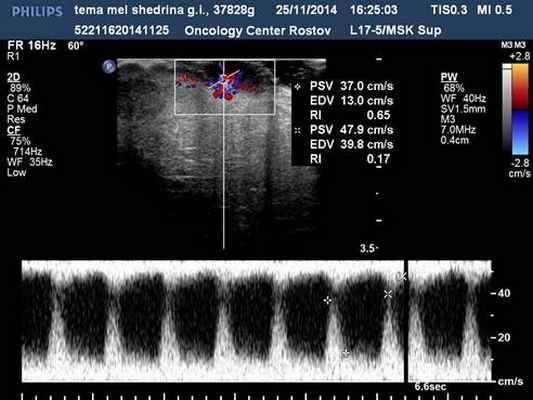

Узловые формы меланом (у 28 чел.) кожи в 100 % наблюдений характеризовались округлой формой, пониженной эхогенностью, неоднородной структурой, инвазивным ростом, наличием патологического артерио-артериального кровотока различной степени интенсивности (низкой 5 %, средней 14 %, высокой 81 %) с диапазонами максимальных артериальных скоростей (МАС) на уровне от 9,23 до 75,2 см/с, индексом периферического сосудистого сопротивления 0,2–0,6 (рис.1, 2).

Рис. 2. Узловая меланома кожи. Допплерометрия в сосудах опухоли. Патологические артерио-артериальные анастамозы с параметрами пиковых систолических скоростей 37,0-47,9см/с (ИР 0,17–0,65)

Данные доплеровские признаки, с нашей точки зрения, могут быть использованы в качестве надежных диагностических критериев узловой меланомы кожи. Следует отметить, что при узловых меланомах всегда идентифицировалась патологическая ангиоархитектоника в прилежащих латеральных зонах кожи. Выявления особенностей гемодинамики узловых меланом имеет особое значение в планировании характера и объема операции в онкодерматологии [8,10].